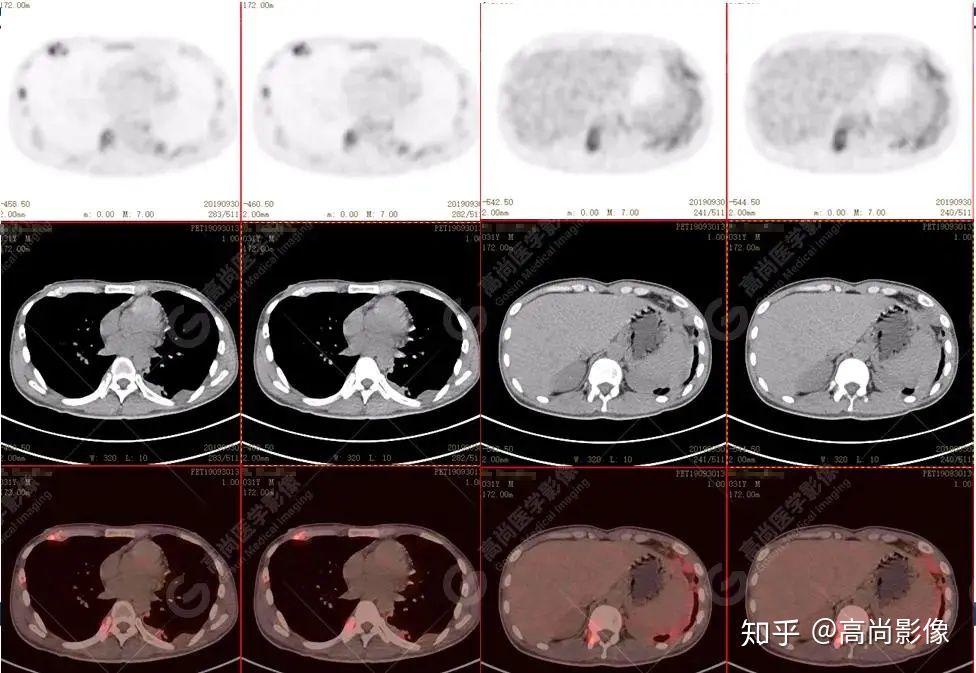

全身多發(fā)高代謝腫大淋巴結(jié),中央代謝缺損

左肺上葉尖后段及下葉背段多發(fā)簇狀斑點狀高代謝灶

左側(cè)胸膜結(jié)節(jié)樣增厚,代謝不同程度增高

【PET/CT提示】雙肺、左側(cè)胸膜多發(fā)結(jié)節(jié)影,全身多處骨質(zhì)破壞,全身多發(fā)淋巴結(jié)腫大,代謝攝取不均勻性增高。